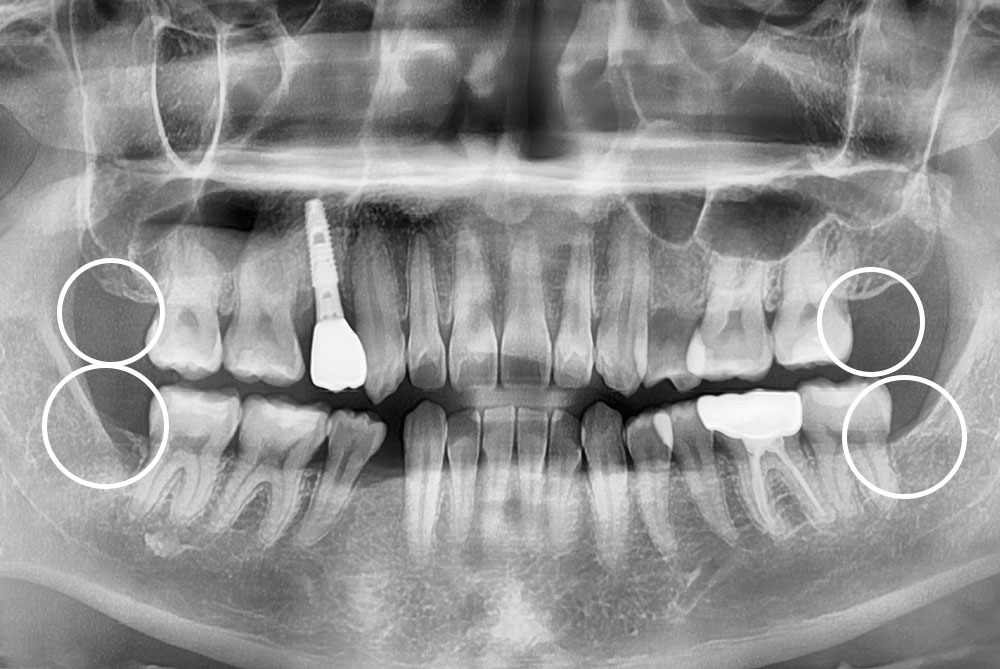

[사랑니] 매복 사랑니 발치

치료전 : 2017-05-09